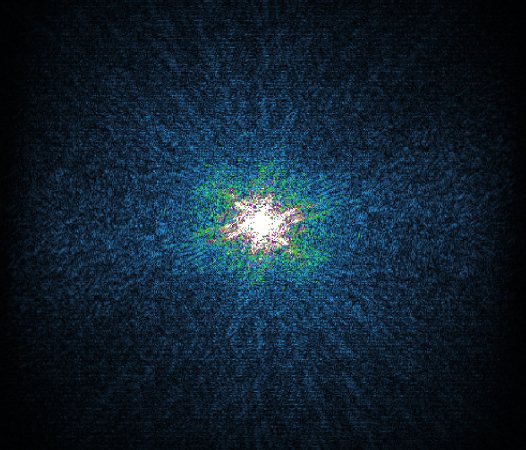

In the example below, only one fifth of the required MR radiofrequency signals is recorded. This results in a five times faster acquisition, with a subsampled k-space (top left) and inherent image artifacts after standard reconstruction (top right).

Basic compressed sensing principle

K space

The Compressed SENSE reconstruction then uses iterative, knowledge-based algorithms to fill in the empty lines in k-space (bottom left). This removes the artifacts while keeping the final image fully consistent with the acquired data (bottom right).